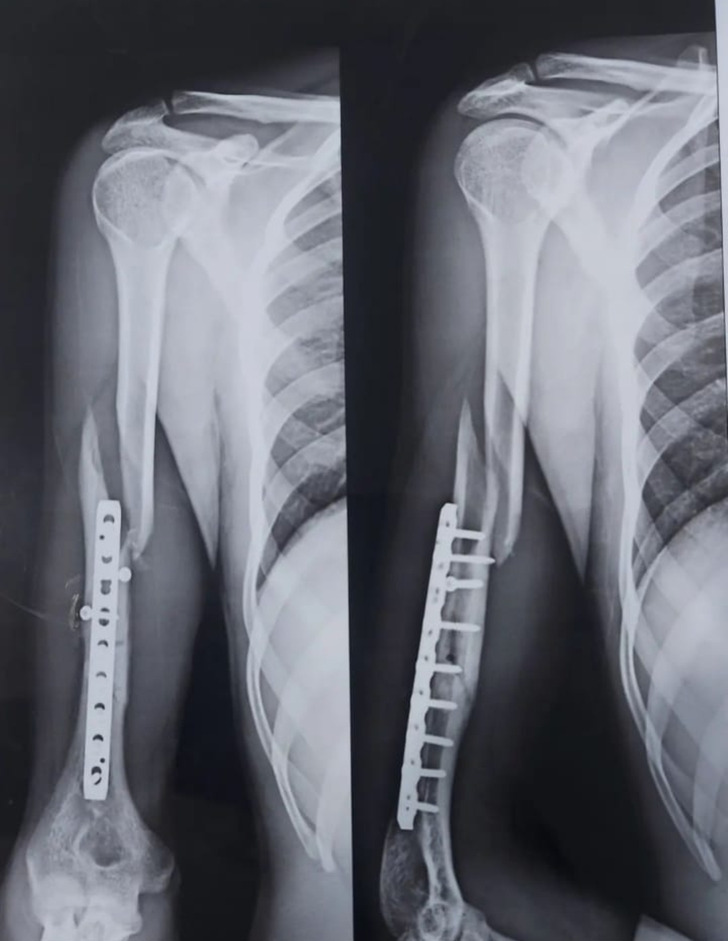

#6 Kamarát si zlomil rameno pri wrestlingu pred tromi mesiacmi a včera si ho zlomil opäť pri tenise